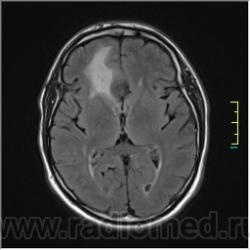

Пациентка направлена на исследование с диагнозом "Гипертонический криз"

Пациентка направлена на исследование с диагнозом "Гипертонический криз", энцефалопатия неуточненная.

частично функционирующая аневризма

Иначе говоря, аневризма с хронической геморрагией, т.к. мы видим фракции крови различного возраста.

По-моему, аневризма с пристеночными тромбами.

Постепенное пристеночное образование тромбов приводит к появлению типичного для аневризмы феномена -слоистости МР сигнала в полости аневризмы. Данная картина демонстрирует слоистый характер тромботических масс в полости аневризмы .Функционрирующая часть имеет низкий сигнал во всех режимах сканирования. Дополнительно-перифокальный отек.

А может более корректно интерпретировать как частично тромбированная аневризма... Уж коь речь идет о фракциях, ну то есть о тромбе по сути.... Ну и плюс перфокальный отек головного мозга (вероятнее цитотоксический+вазогенный).